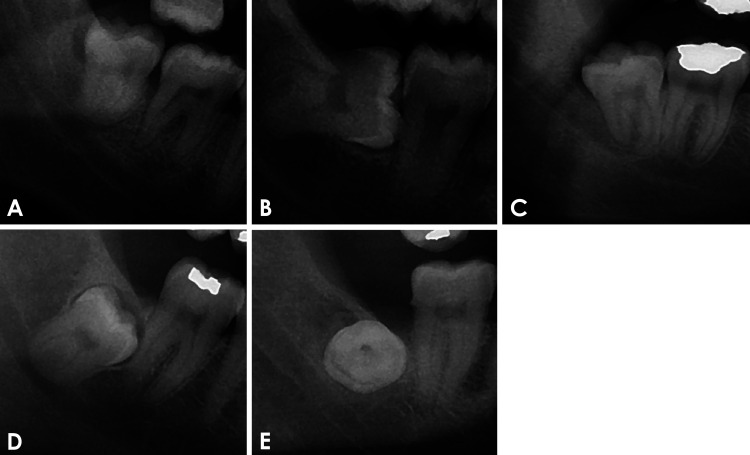

Abstract Image